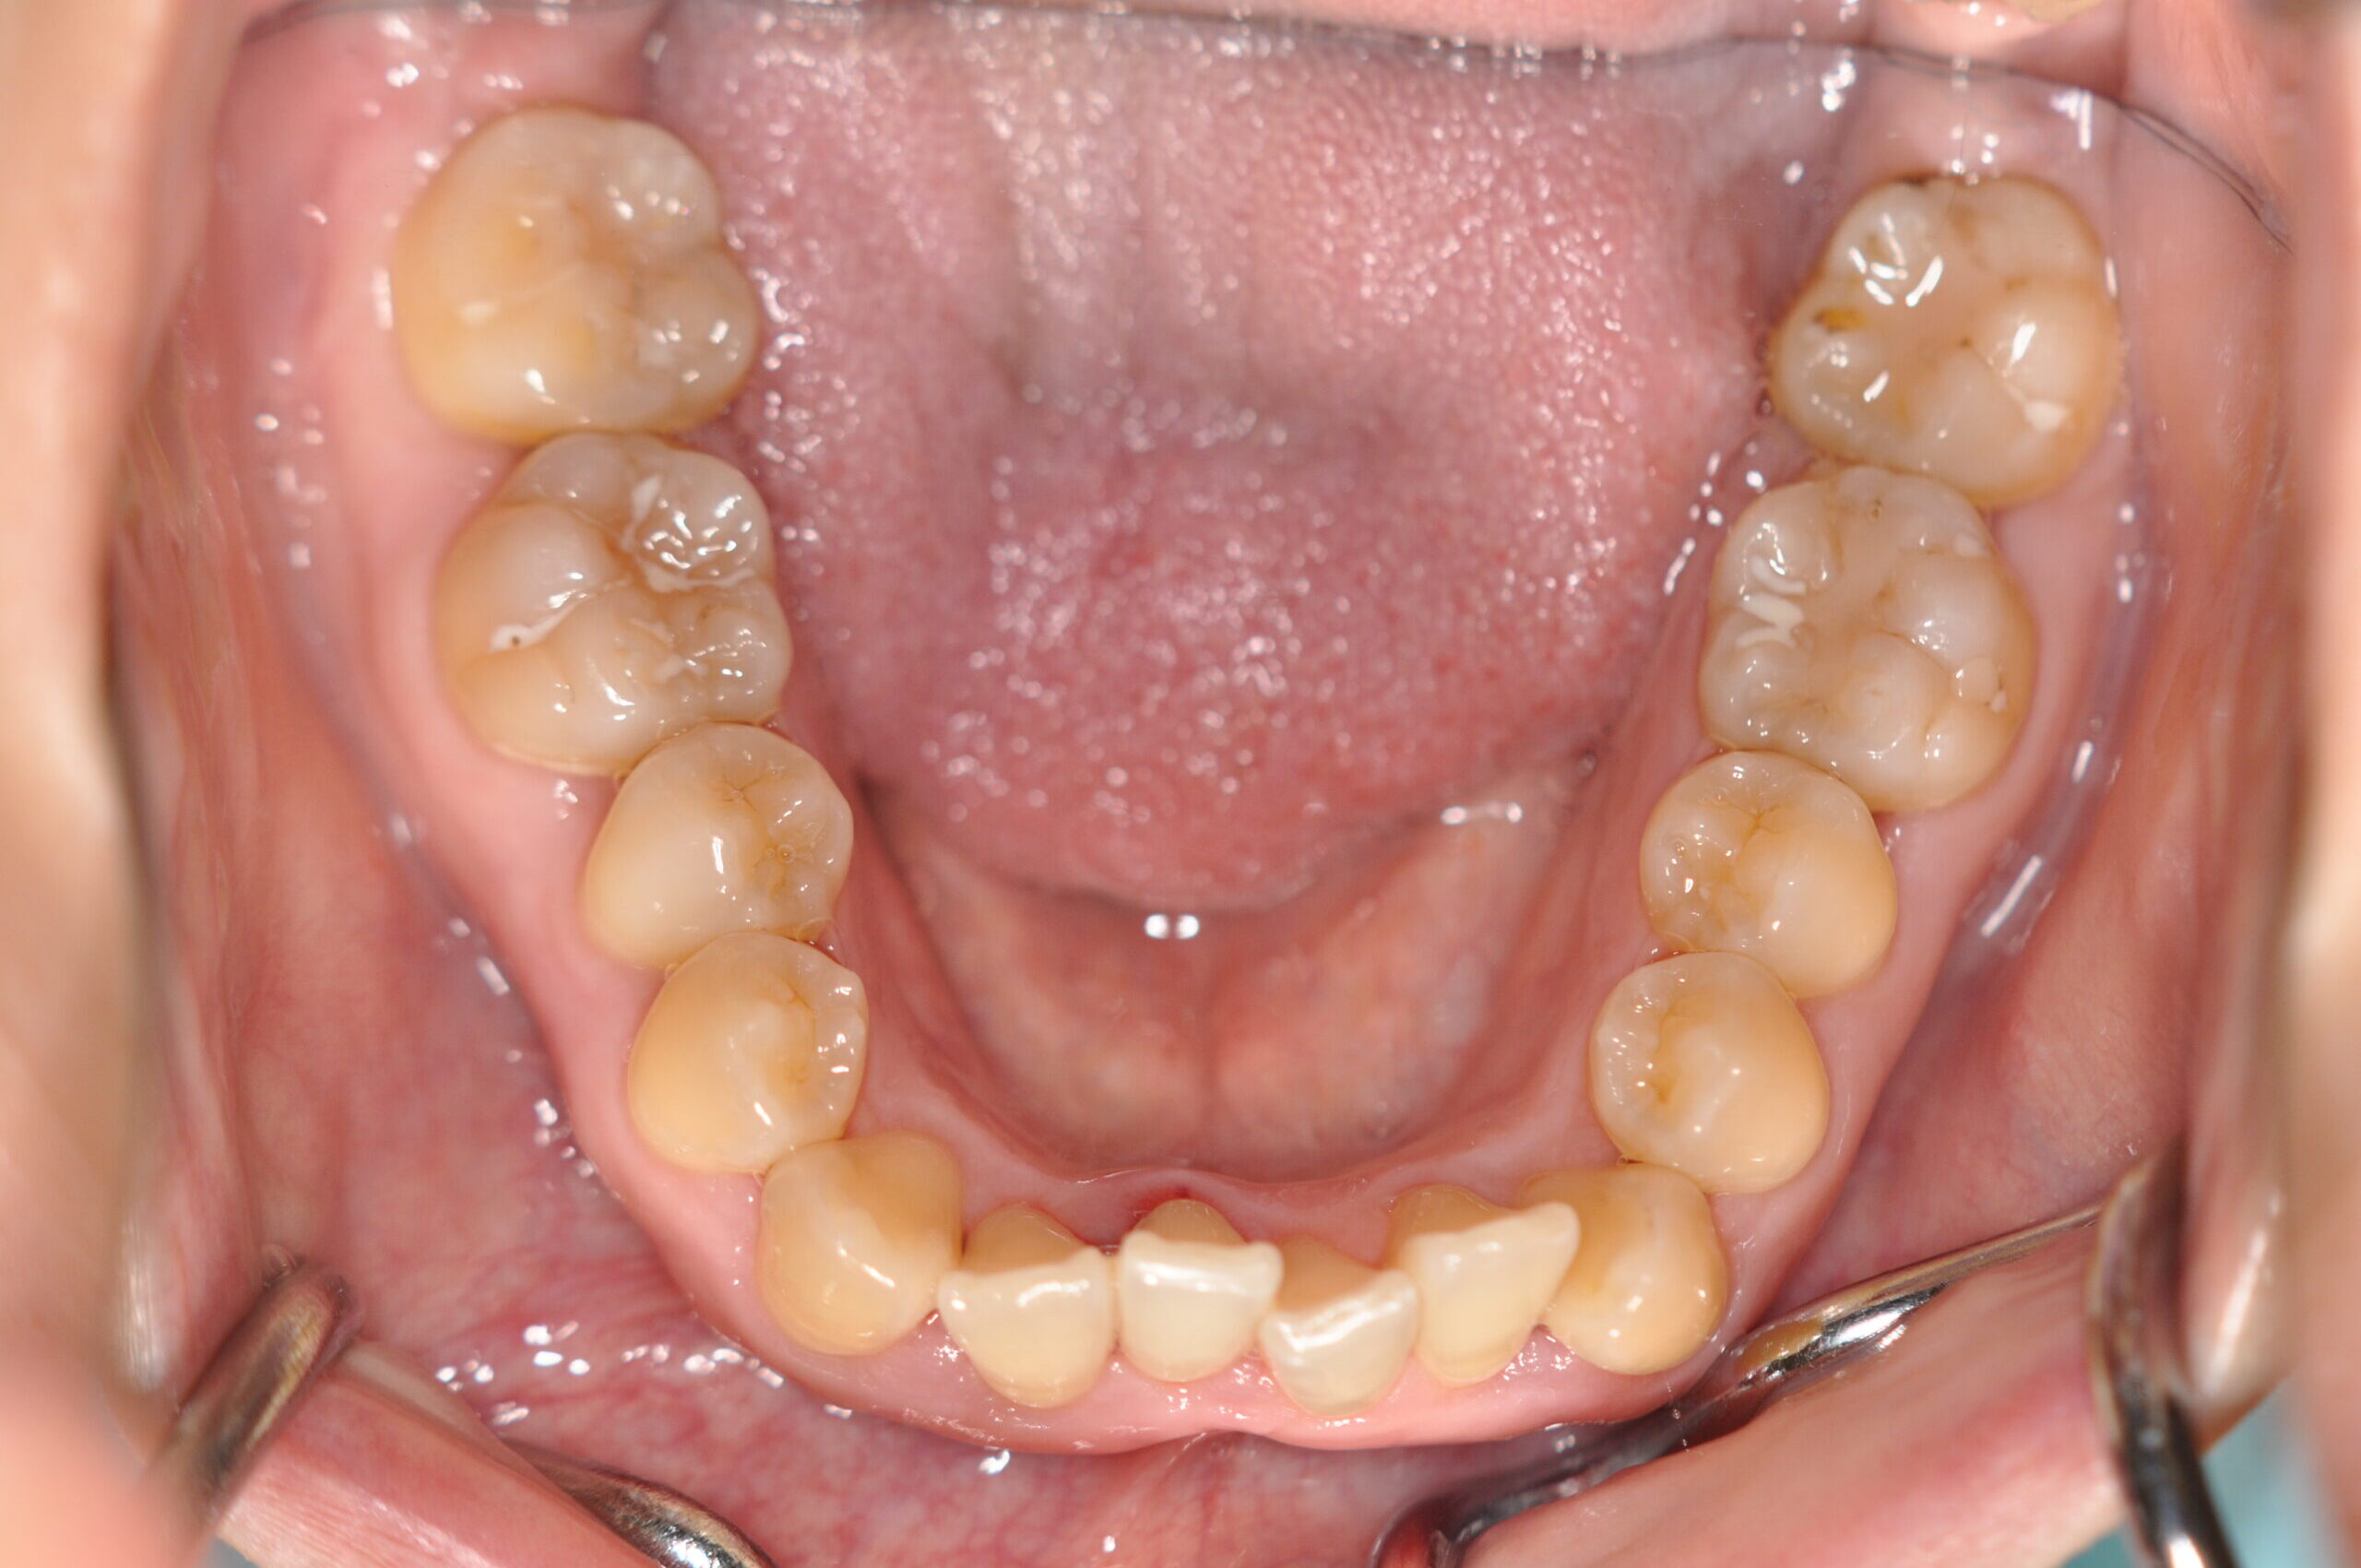

叢生(非抜歯)[2590]

初診時

年齢

31歳10ヶ月 性 別 女性

治療期間 2年7ヶ月 費 用 矯正施術料:1,000,000円 調整料:4,000円/月

治療内容の詳細 初診時31歳の女性で、前歯が奥側にあることを気にされ来院されました。

検査の結果、上下顎叢生を伴うアングルⅠ級不正咬合と診断しました。

治療としては、上顎臼歯部の遠心移動を行い、歯を配列するためのスペースを確保し、非抜歯の上、セルフライゲーションブラケット装置(デーモンシステム)で歯の配列と咬合関係の改善をを行いました。

治療期間は、2年7ヶ月でした。